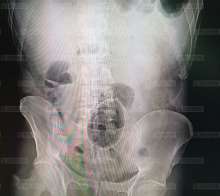

Яйцо.jpg (45Кб, 558x418)

Чудо.jpg (52Кб, 557x497)

На выходных бригада скорой помощи привезла в одну из клиник Петербурга 40-летнего мужчину. У него в прямой кишке застряло пасхальное деревянное яйцо, сообщает "Пятый канал".

Пострадавший не смог объяснить медикам, как сувенир туда попал. Мужчина долго не мог обратиться за помощью. Они с супругой шесть часов пытались достать яйцо, но у мужчины в результате открылось сильное кровотечение.